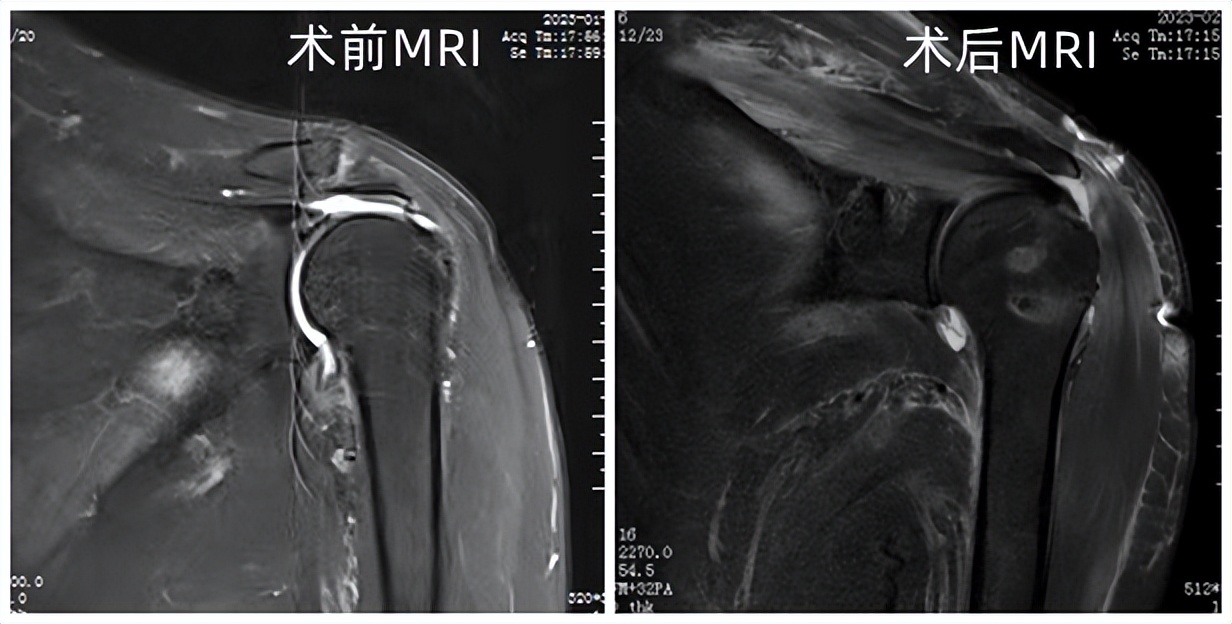

王全兵接诊后,初步判断周大爷是肩袖损伤,磁共振检查验证了他的判断,并确定老人已达到巨大肩袖损伤的程度。王全兵介绍,肩袖是由冈上肌、冈下肌、肩胛下肌、小圆肌肌腱分布在肩关节前、后、上方包绕肩关节形成的袖套样的组织。每一根肌腱都在肩关节内收、外展、前屈、后伸、上举、环转中起到重要作用,任何一根肌腱损伤,其所对应的功能则明显减弱,肌腱损伤就造成了肩袖损伤。

针对周大爷的情况,王全兵团队采取肩袖缝合、肌腱转位等方式,在肩关节镜下,通过微创手段,先对萎缩的肌腱进行松解,让肌腱尽可能复位,然后予以缝合,对不能完全复位的肌腱采用肌腱转位固定。两个小时后,手术完成,周大爷肩关节疼痛立刻得到缓解,在他人的帮助下可以实现手臂自由活动。